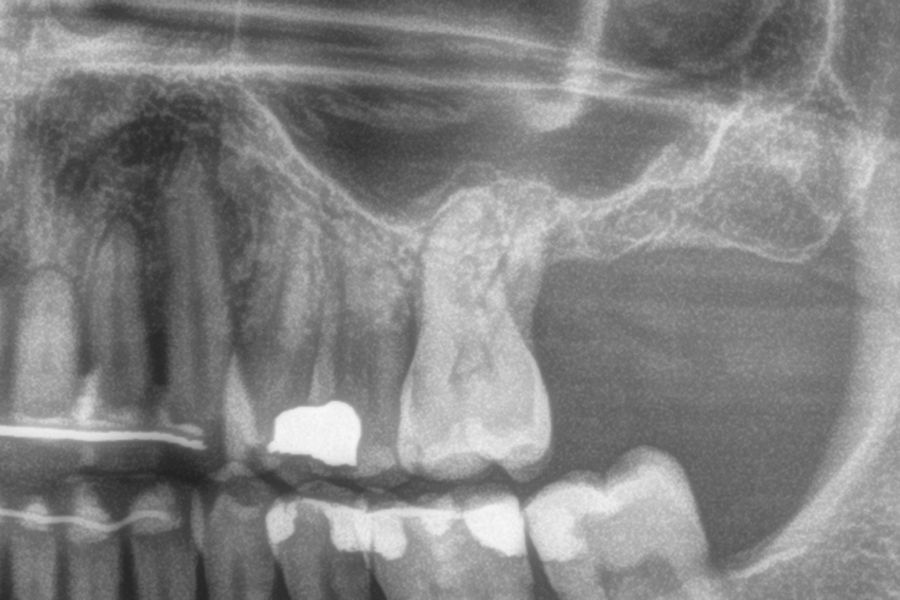

In all cases, a diagnosis was made based on study models, intraoral examination of the patient and performing a Cone-beam analysed using the specific BTI-Scan 3 software (Biotechnology Institute, Vitoria, Alava, Spain).

Ten patients who met the inclusion criteria were recruited, in which 20 implants were inserted. Three of them were women with an average age of 72 (+/- 6 years). None of the patients were smokers at the time of surgery and did not have any active periodontal disease. The majority of the implants diameter included in the study was 5 mm (60%), followed by 4.5, 5.5 and 4.75 mm (13.33% each). The predominant length was 5.5 mm (86.6% of the cases), with 13.4% of the remaining implants with a length of 4.5 mm. The most common positions were for the second molars (molars 27 and 17) representing 55% of the cases.

Figures 2-19 show one of the cases included in the study.